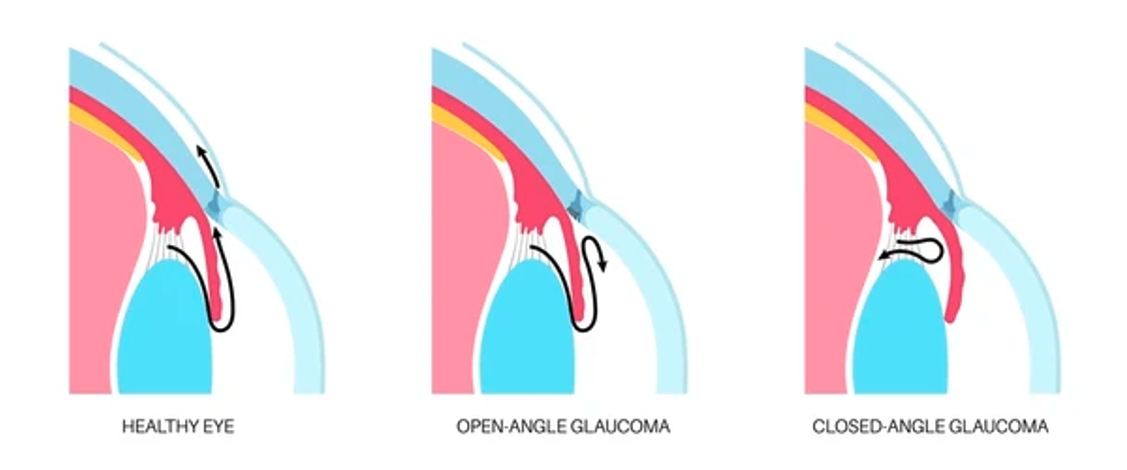

Les deux principaux types de glaucome sont le glaucome à angle ouvert et le glaucome à angle fermé.

– Glaucome à angle ouvert : ce type est le plus fréquent. Il se développe lentement et ne présente souvent aucun symptôme au début. Dans le glaucome à angle ouvert, le liquide intraoculaire s’écoule moins efficacement, ce qui entraîne une augmentation de la PIO. Les patients ne remarquent généralement les effets que lorsqu’une partie importante de leur vision est déjà perdue.

– Glaucome à angle fermé : ce type est moins courant, mais constitue une urgence médicale. Il touche particulièrement les patients forts hypermétropes ou avec une cataracte avancée. Dans l’angle fermé, l’angle entre l’iris et la cornée est trop étroit, bloquant le drainage du liquide intraoculaire (humeur aqueuse) et provoquant une montée rapide de la PIO. Les symptômes incluent des douleurs oculaires sévères, des nausées, une vision floue, et des halos autour des lumières. Sans intervention immédiate, ce type de glaucome peut entraîner une perte rapide de la vision.

-Gonioscopie : cette technique évalue l’angle irido-cornéen pour déterminer le type de glaucome (ouvert ou fermé).